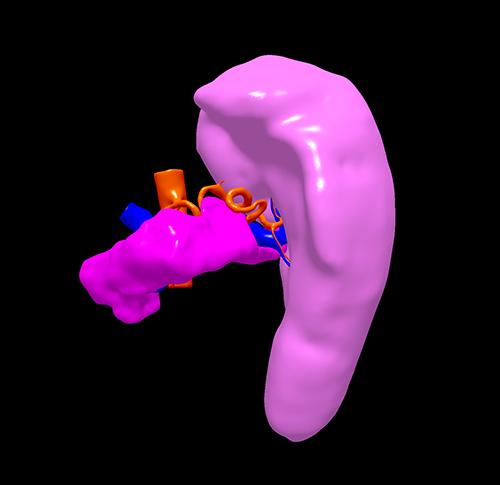

遗传性球形红细胞增多症--腹腔镜脾切除